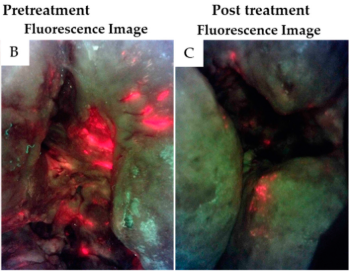

Lights, fluorescence, action—Influencing wound treatment plans including debridement of bacteria and biofilms

Jacob, A et al. Int Wound J 2023

Use of a bacterial fluorescence imaging device: wound measurement, bacterial detection, and targeted debridement

Raizman, R et al. J Wound Care 2019

Use of a bacterial fluorescence imaging system to target wound debridement and accelerate healing: a pilot study

Cole, W and Coe S. J Wound Care 2020

Prospective clinical study on the efficacy of bacterial removal with mechanical debridement in and around chronic leg ulcers assessed with fluorescence imaging

Moelleken, M et al. Int Wound J 2020

How effective is simple mechanical wound debridement in reducing bacterial colonisation? Results of a prospective clinical study

Moelleken, M et al. Int Wound J 2024